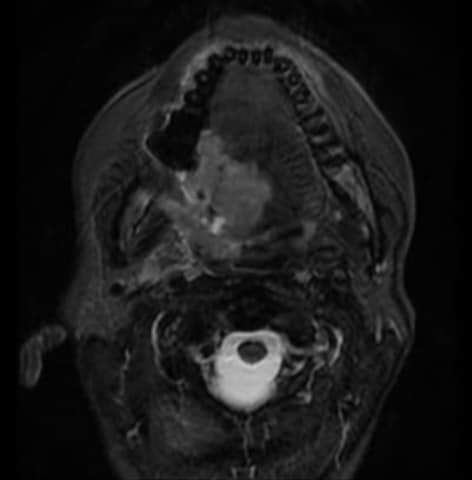

Al igual que la TC (tomografía computada), las imágenes por resonancia magnética muestran imágenes detalladas de los tejidos blandos del cuerpo. Utilizan ondas de Radio e imanes potentes en lugar de rayos X. Debido a que provee una imagen detallada, puede que se haga una Resonancia Magnética para determinar si hay propagación de cáncer en el cuello.

- Resonancia Magnética de Cuello 6 julio, 2022